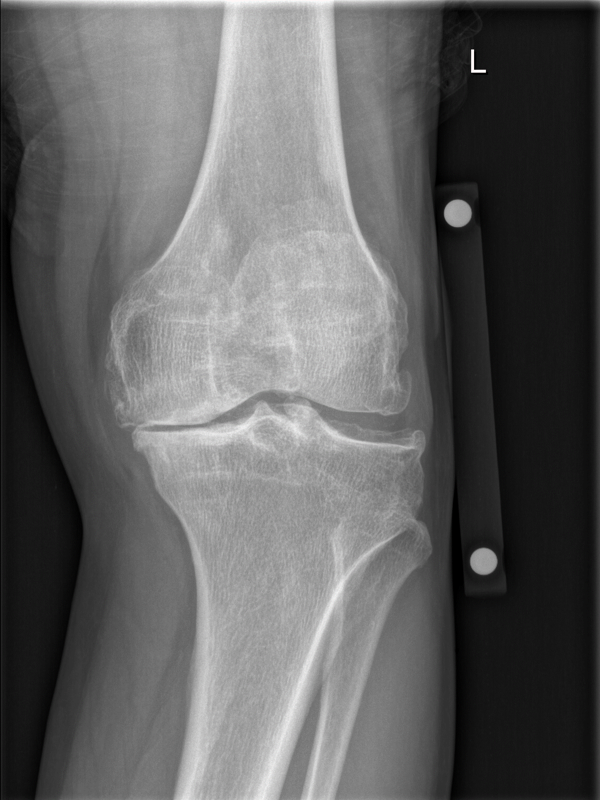

双侧膝关节间歇性疼痛6年余,加重半年余 患者6年前出现下楼时膝关节隐痛,间歇性发作。平地行走时未感疼痛。于外院行MR检查,建议手术治疗。患者自觉症状较轻,药膏敷贴症状可缓解。暂时保守治疗。今年患者疼痛症状加重,休息时也感觉膝关节疼痛。阴雨天时疼痛加重,需拄拐行走,约200m需要停下休息

双侧下肢力线可,膝关节轻度肿胀。皮温略高。轻度屈曲畸形,活动度可。 X片提示 双侧膝关节退行性病变

膝关节OA 左侧膝关节全膝置换术(TKA)